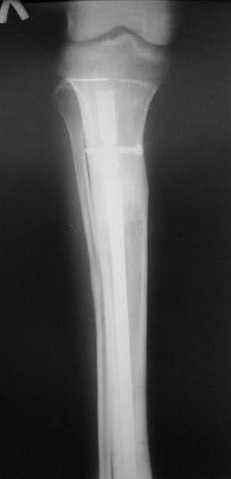

5. Ну и чтобы не быть голословным. Молодой человек подорвался на фугасе (Чечня, 2005 год). Свежие рентгенограммы:

Соответственно ожоги и дефект мягких тканей, переломы костей стопы и пр. Наложили аппарат

Илизарова (как придется), хирургически обработали и героически заживляли мягкие ткани с многочисленными кожными пластиками. В итоге через полгода я принял его вот таким: